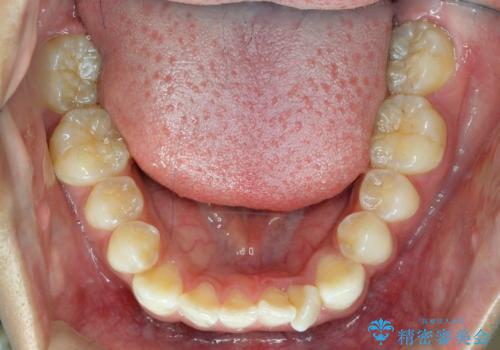

前歯のがたつき 1年かからず治療 マウスピース矯正

- 前歯のがたつきを主訴に来院。

インビザラインで歯を抜かずに並べました。

マウスピースの延長(リファインメント)もなく、短期間で綺麗に並びました。